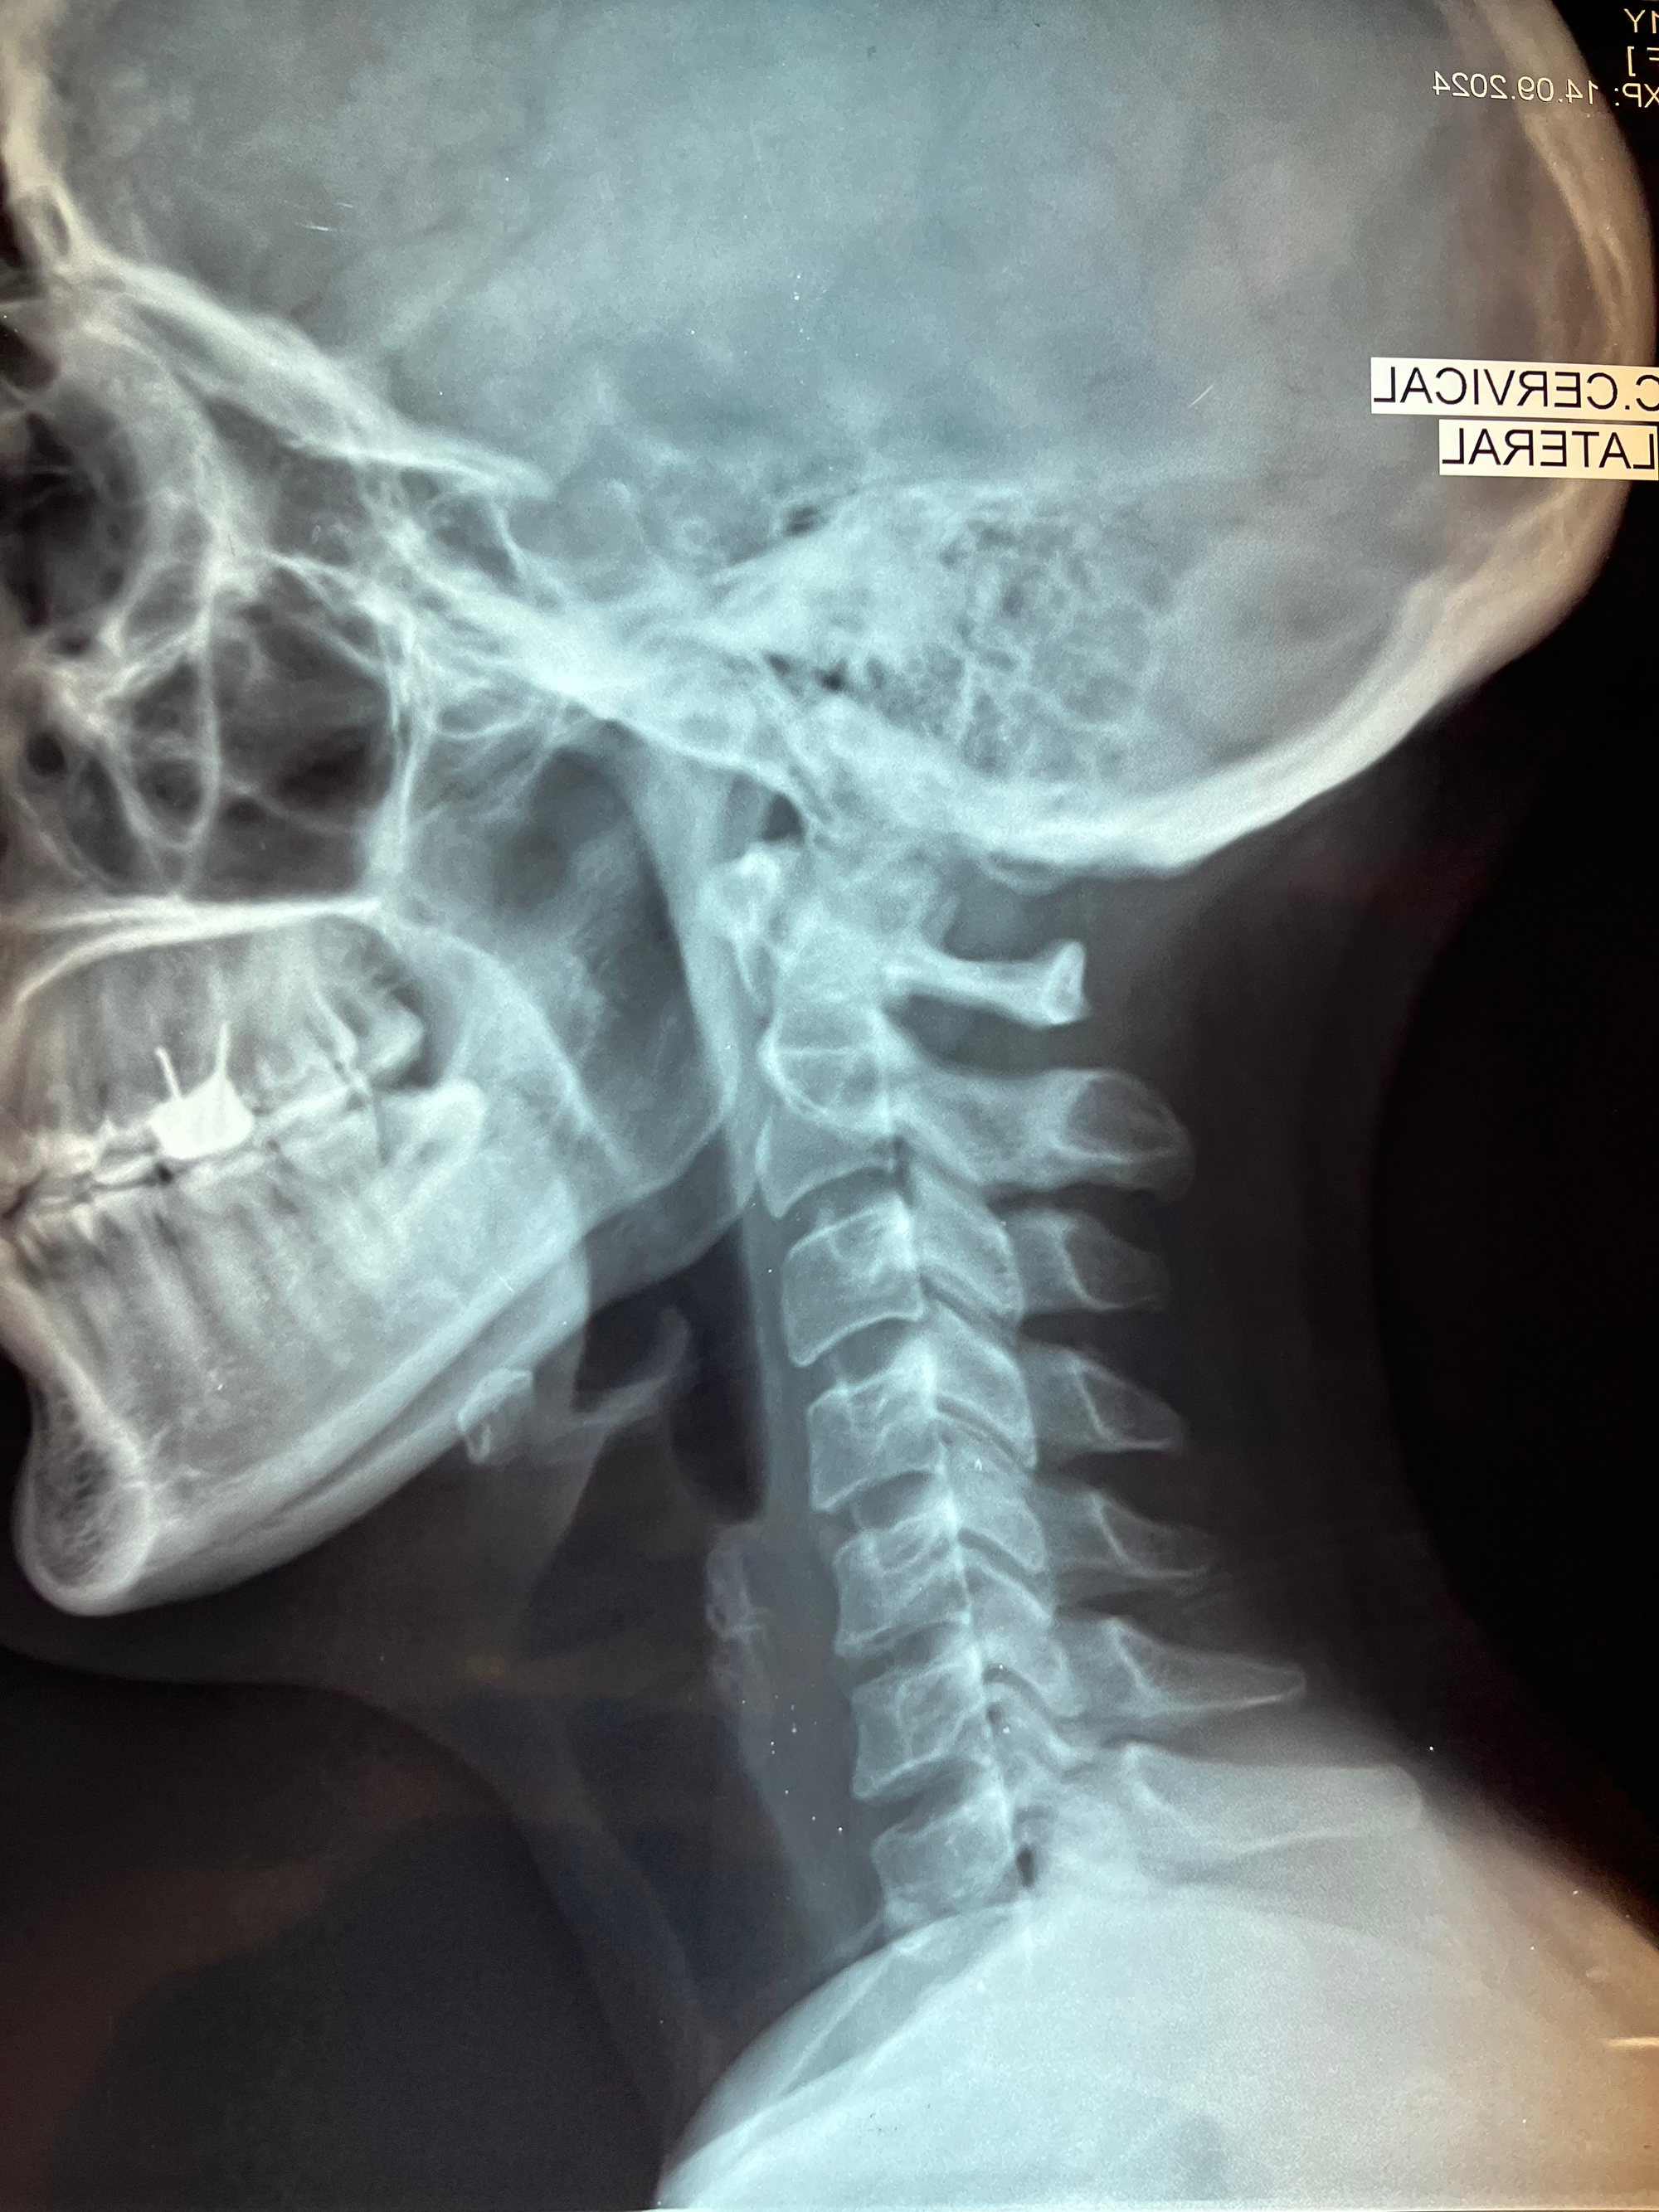

Analizar tu columna es muy importante para identificar la causa de tu dolor y prevenir cambios degenerativos o estructurales que puedan afectar tu calidad de vida y adecuado funcionamiento de tu cuerpo.

utilizamos los estudios competentes para brindar un diagnóstico preciso sobre las condiciones de tu columna.